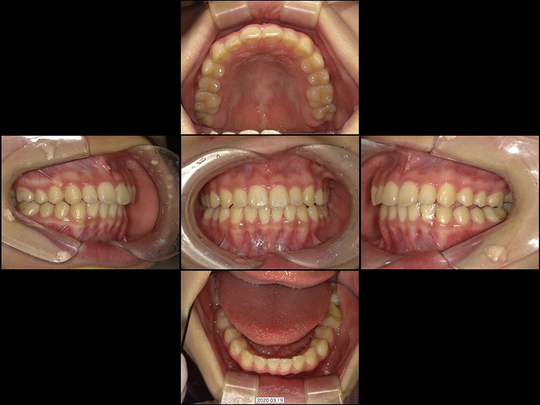

Wさん 10代 女性

矯正前

矯正後

あごをどんなに動かしても前歯で咬めない、というケースです。

将来的に奥歯に負担がかかりやすい咬み合わせであるため、矯正治療の対象ではあったものの、まずは著しい舌の悪習癖を改善する必要がありました。「タングガード」とよばれる舌を抑える柵を併用し、非抜歯にてマルチブラケット装置を使用して対応しました。

治療の期間・回数

20か月、24回

​費用

720,000円

リスクや副作用:まれに歯の根が短くなる可能性があります。装置装着後、痛みを感じることがあります(歯が動く正常な反応なので心配ありません)。頬の粘膜・唇・舌などに、口内炎ができることがあります。歯周病等で歯ぐきが下がっている方は、歯を動かすことでさらに歯ぐきが下がる可能性があります。重なっていた歯がきれいに並んだことで歯ぐきと両隣の歯との間に三角形の隙間ができる可能性があります。